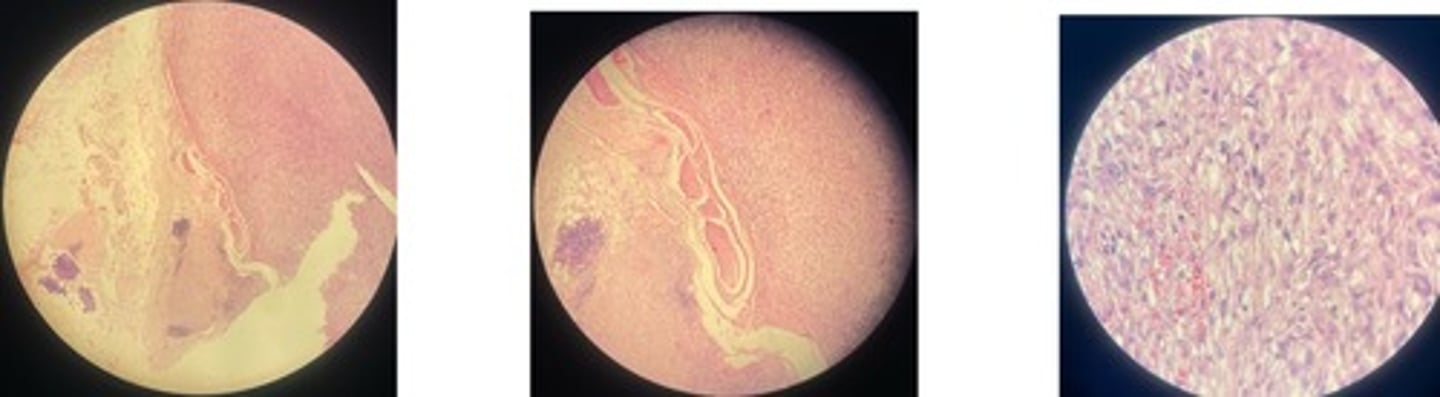

Catarrhal Bronchopneumonia

· thick bronchide walls

· catarral exudate in alveoli lumen (RBCs, leukocytes + mucous)

· congested vessels

· edema separates good + bad

Fibrinous Bronchopneumonia => mosaic appearance

· Acute = capillaries congested + alveoli filled w/light pink fluid

· Red = alveoli filled w/ exudate = fibrin + RBCs

· Grey = lots of neutrophils in lumen

· Resolution = fibrin in strands due to neutrophils enz release